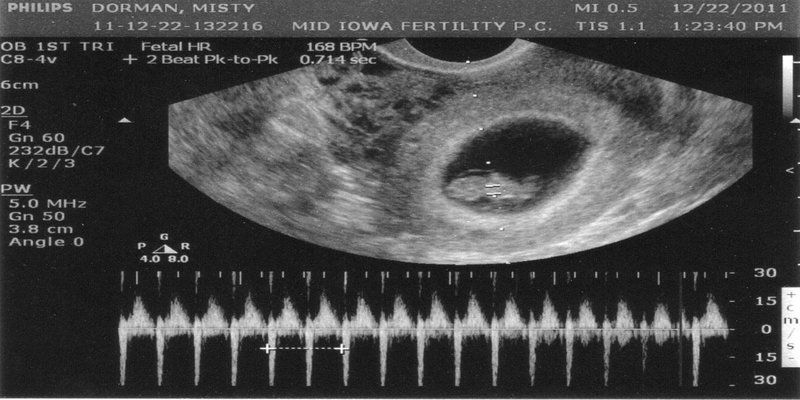

3. Nhịp Tim Thai 6 Tuần Bao Nhiêu Là Bình Thường?

Nhịp tim thai 6 tuần tuổi thường dao động từ 90 – 120 nhịp/phút. Tuy nhiên, tốc độ này có thể thay đổi và tăng dần trong các tuần tiếp theo. Nếu nhịp tim dưới 90 nhịp/phút, bác sĩ có thể chỉ định theo dõi để đảm bảo thai nhi phát triển bình thường.

4. Siêu Âm Tim Thai 6 Tuần

a. Phương Pháp Siêu Âm

Có hai phương pháp siêu âm phổ biến để kiểm tra tim thai:

- Siêu âm ổ bụng: Áp dụng cho những thai phụ có thành bụng mỏng, nhưng ở tuần thứ 6, phương pháp này có thể chưa phát hiện rõ nhịp tim.

- Siêu âm đầu dò âm đạo: Cho kết quả chính xác hơn về tim thai, đặc biệt là trong giai đoạn sớm của thai kỳ.